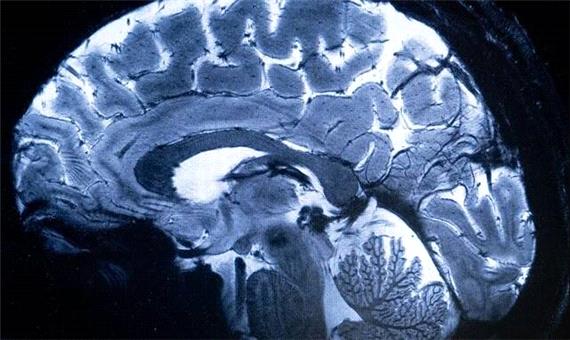

سیاست و بازاریابی - ایسنا / چهاردهمین کنگره علوم اعصاب پایه و بالینی با حمایت ستاد توسعه علوم و فناوریهای شناختی از 19 آذر در تهران گشایش می یابد.

چهاردهمین کنگره علوم اعصاب پایه و بالینی به منظور توسعه فعالیتهای پژوهشی، تبادل آخرین دستاوردها و یافته های تحقیقاتی و نیز گسترش تعامل و همکاری میان محققان، متخصصان و پژوهشگران با حمایت ستاد توسعه علوم و فناوریهای شناختی از 19 تا 21 آذرماه در محل مرکز همایشهای بین المللی رازی دانشگاه علوم پزشکی ایران برگزار می شود.

ارائه جدیدترین دستاوردهای علمی و نتایج تحقیقاتی با حضور متخصصان برجسته داخلی و بینالمللی در تمامی رشتههای مرتبط از مهندسی تا پزشکی و علوم انسانی از رویکردهای این گردهمایی تخصصی به شمار می رود.